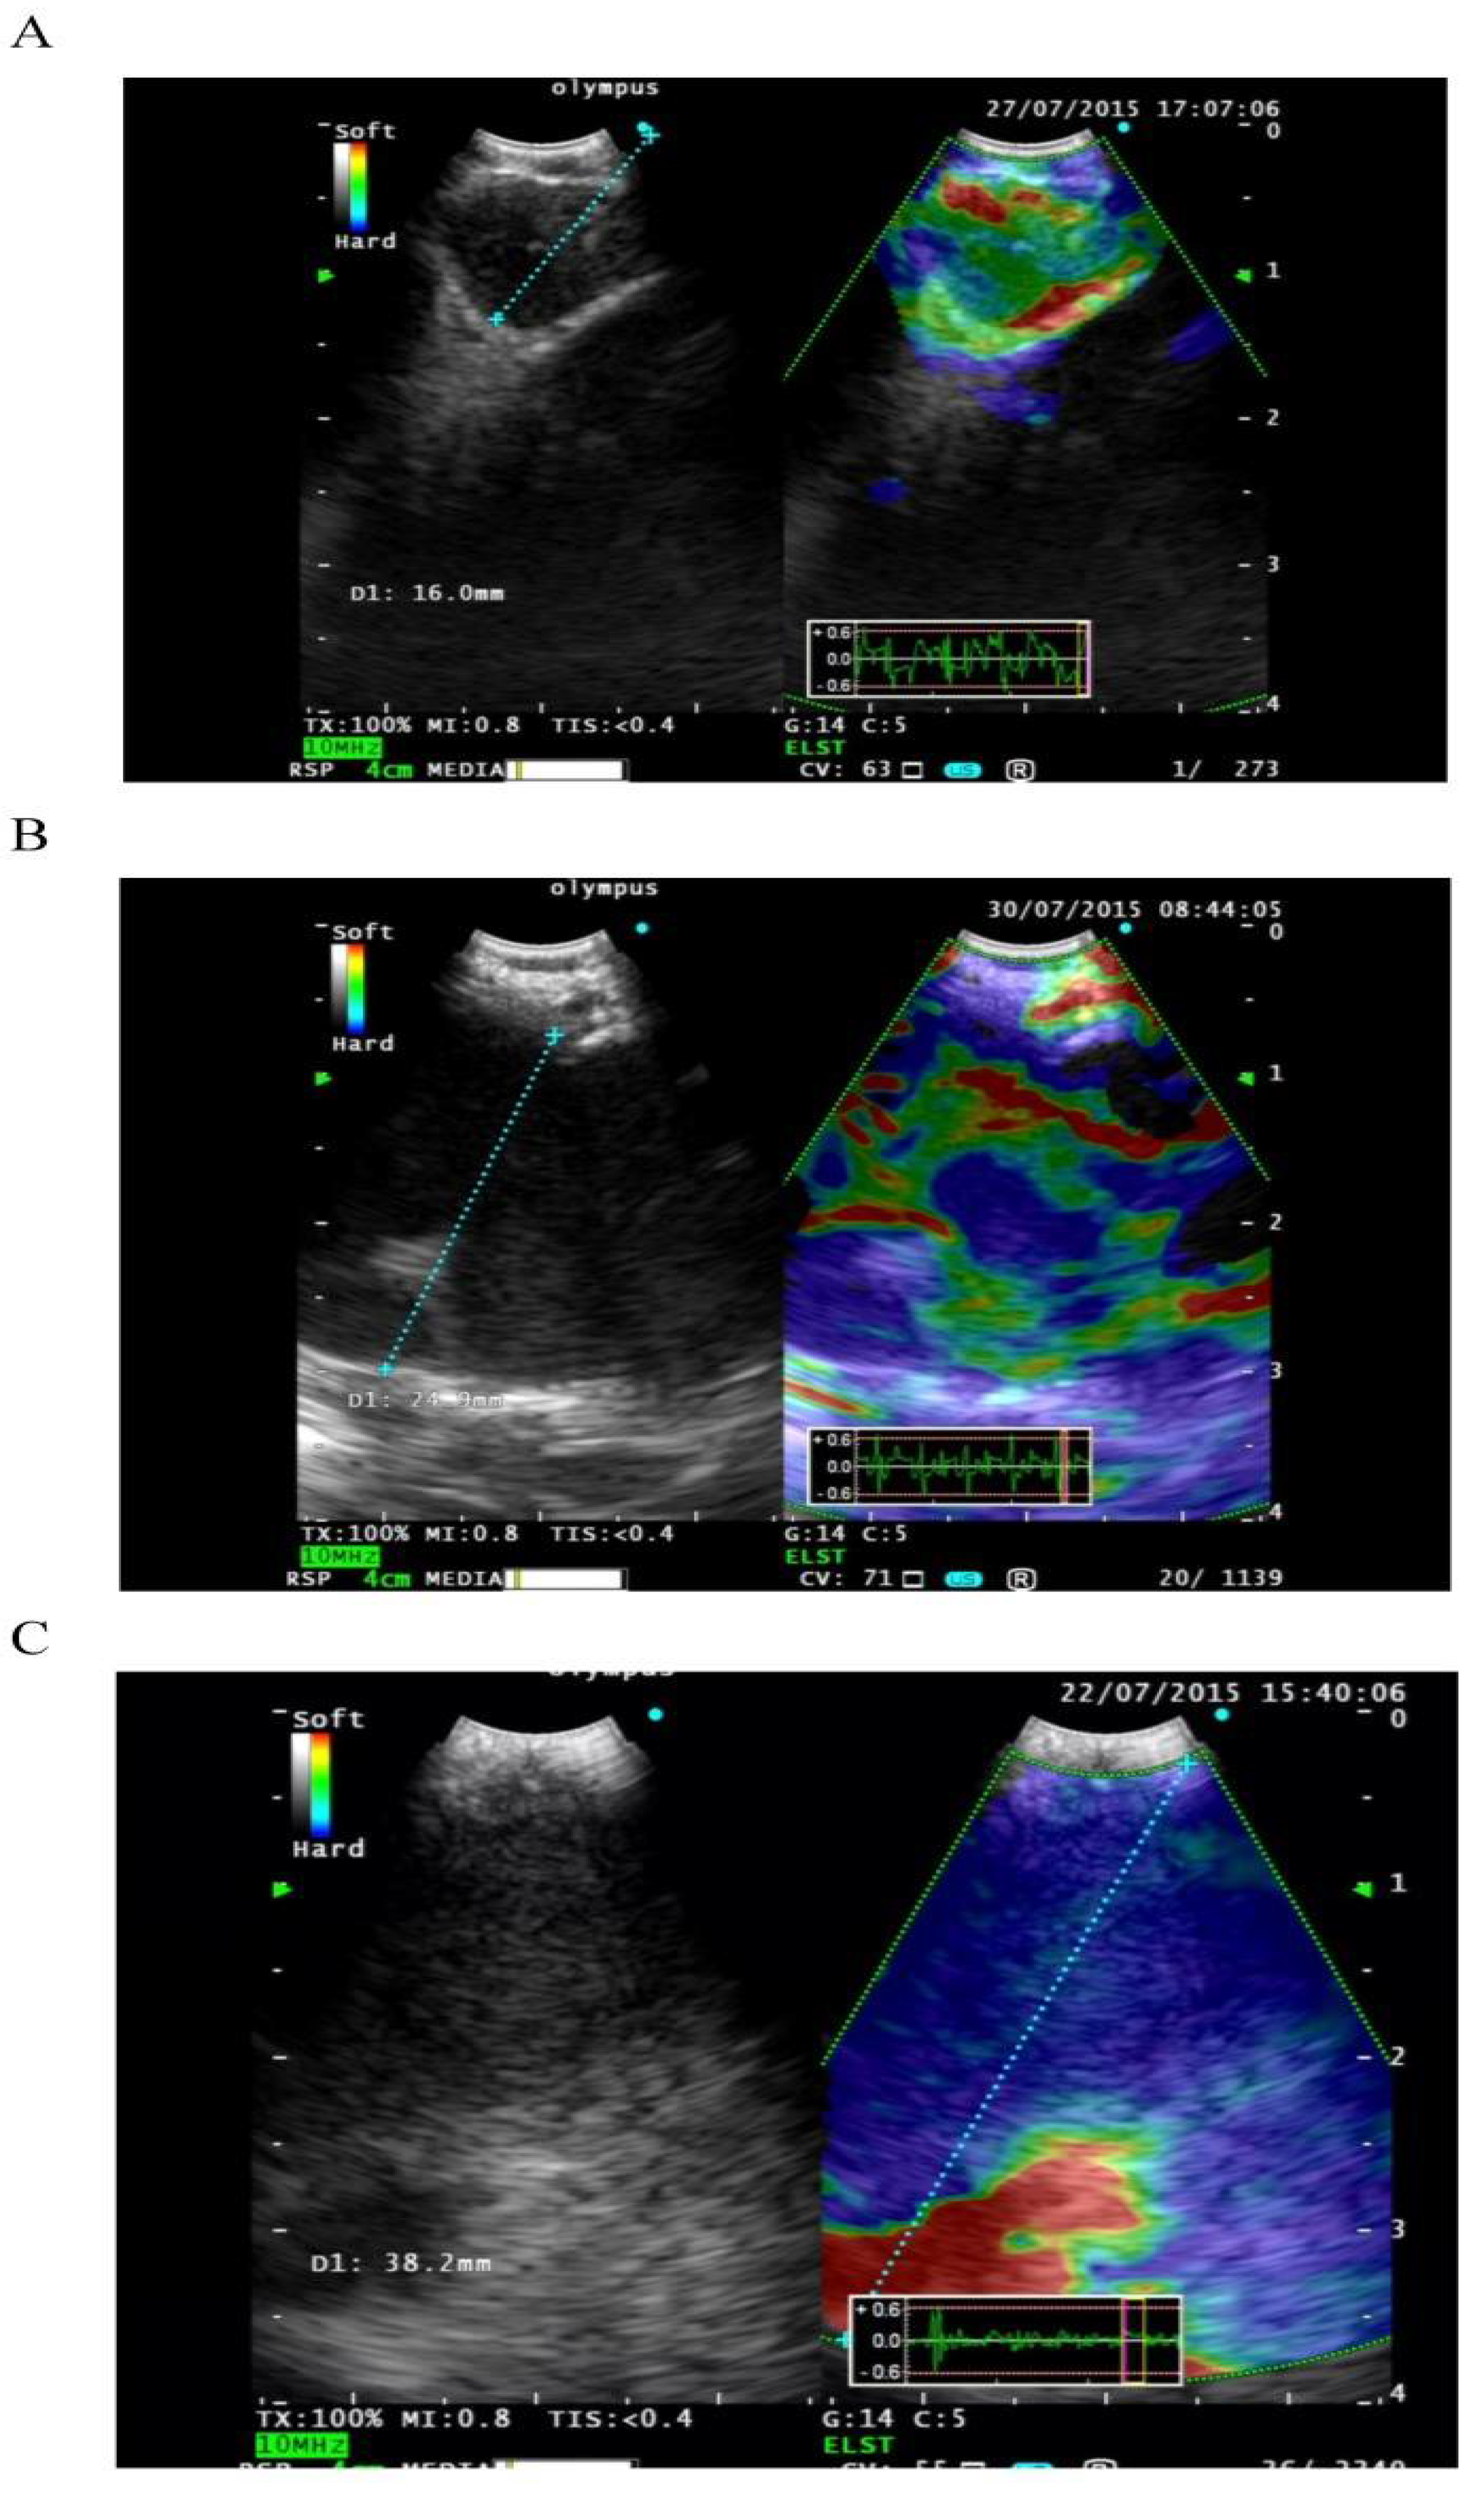

2.8. EBUS Elastography

- Korrungruang, P.; Boonsarngsuk, V. Diagnostic value of endobronchial ultrasound elastography for the differentiation of benign and malignant intrathoracic lymph nodes. Respirology 2017, 22, 972–977. [Google Scholar] [CrossRef]

- Izumo, T.; Sasada, S.; Chavez, C.; Matsumoto, Y.; Tsuchida, T. Endobronchial ultrasound elastography in the diagnosis of mediastinal and hilar lymph nodes. Jpn. J. Clin. Oncol. 2014, 44, 956–962. [Google Scholar] [CrossRef]

- Huang, H.; Huang, Z.; Wang, Q.; Wang, X.; Dong, Y.; Zhang, W.; Zarogoulidis, P.; Man, Y.-G.; Schmidt, W.H.; Bai, C. Effectiveness of the Benign and Malignant Diagnosis of Mediastinal and Hilar Lymph Nodes by Endobronchial Ultrasound Elastography. J. Cancer 2017, 8, 1843–1848. [Google Scholar] [CrossRef]